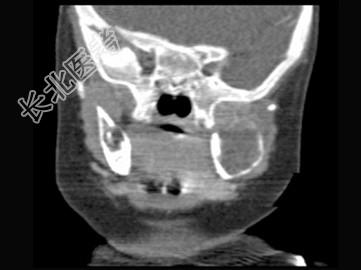

- 单项选择题男,2岁, 左侧颜面部、右肩部肿块,疼痛, 结合图像,最可能的诊断是 ( )

A、骨结核

B、骨髓炎

C、骨嗜酸性肉芽肿

D、骨囊肿

E、骨肉瘤